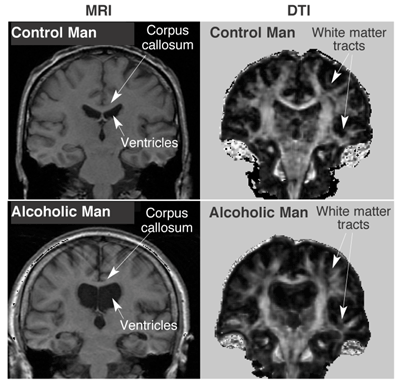

Edellä on esitetty suoranaista dataa siitä että Kyrde osaa kirjoittaa googleen "effects of alcoholism on brain", painaa kuvat- välilehden auki ja peistailla sieltä kuvia. Siitä miten alkoholi vaikuttaa aivoihin yksittäiset A/B pelotteluvalistuskuvat ei kerro yhtään mitään. Saahan sitä uskoa että "koska näin kuvan jossa on 43v alkoholisti-miehen aivot jotka oli muusia, se tarkoittaa että kaikkien alkoholistien aivot on muusia". Jos pelon takia ei dokaa, niin lopputuloshan on ihan yhtä hyvä joka tapauksessa. Ei tässä asiassa ole ns. "väärin sammutetettua". Mutta jos ottaa esim. tuon artikkelin jossa oli normaalin kuolleen aivot, altzheimeriin kuolleen aivot ja viimeisenä alzheimeriin JA alkoholismiin kuolleen aivot, itse tekstissä puhutaan nimenomaan siitä että aivot korjaavat itsensä ja vaikutukset eivät ole peruuntamattomia toisin kuin ikääntymisen ja AD:n (Alzheimers Disease), jotka ovat peruuttamattomia: In contrast to aging and AD, alcohol's effects on the brain may be reversible (Carlen and Wilkinson 1987). Atrophy decreases after abstinence from alcohol (Kril and Halliday 1999). A study that further investigated cerebral atrophy in alcoholics and age-matched control subjects found no significant differences in the number of nerve cells in the brain (i.e., neurons) between the two groups and that most of the loss occurred in the white matter, which consists largely of nerve fibers that connect neurons (Jensen and Pakkenberg 1993). The researchers concluded that, because neurons did not appear to be lost, disrupted functions could be restored after abstinence as neuronal connections were reestablished. This conclusion is supported by research that also showed no neuronal loss in alcoholics compared with nonalcoholics but did show significant loss of brain cells that provide support for neurons (i.e., glial cells) which, in contrast to neurons, can be regenerated (Korbo 1999). That alcoholics can show improved cognitive performance after abstinence provides additional evidence of a reversible effect (Reed et al. 1992). Jos ihmisellä on huoli että tekeekö viinan juonti yleisellä tasolla jotain peruuttamatonta aivoille, niin kyllä siihen vastaus on "useimmiten ei tee". Jos taas MRI- koneeseen lyödään spurgu, niin tottakai ne aivot on karmean näköiset.